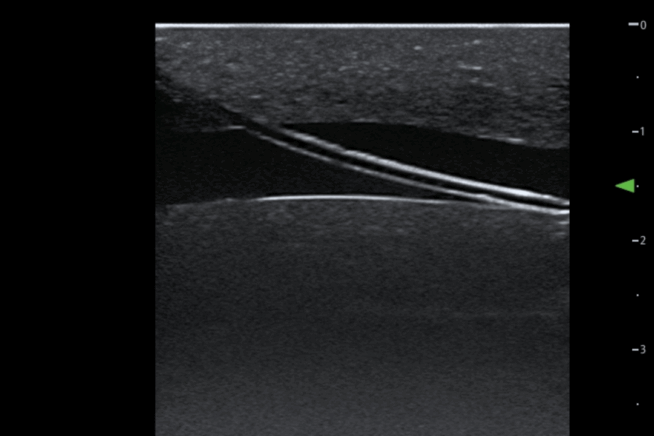

TruCVC® ideal for ultrasound-guided central venous catheterisation training, enabling consistent practice of needle insertion, guidewire handling, and full catheter placement using the Seldinger technique – supported by realistic anatomy, visual flashback, and rapid reset for repeatable learning outcomes.

The TruUltra material is unlike anything else in the market. It showcases a high-quality ultrasound image to provide trainees with a true-to-life ultrasound training solution. Learners will benefit from realistic visualisation of the internal jugular and subclavian veins, carotid and subclavian arteries.

The ultrasound insert facilitates 40+ full catheter incisions (20+ full insertions per site – Jugular vein & Subclavian Vein) using the recommended equipment sizes and 1000+ needle penetrations.

• Size 8Fr (16cm long catheter).

• Size 20G needle for IV cannulation is recommended for optimal performance. Do not use a needle larger than 18G needle.